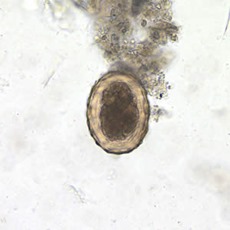

Morfologia – OVOS

Originalmente são brancos e adquirem cor castanha devido ao contato com as fezes. São grandes, com cerca de 50 µm de diâmetro, ovais e com cápsula espessa, em razão da membrana externa mamilonada, secretada pela parede uterina e formada por mucopolissacarídeos.

Ovos férteis de A. lumbricoides